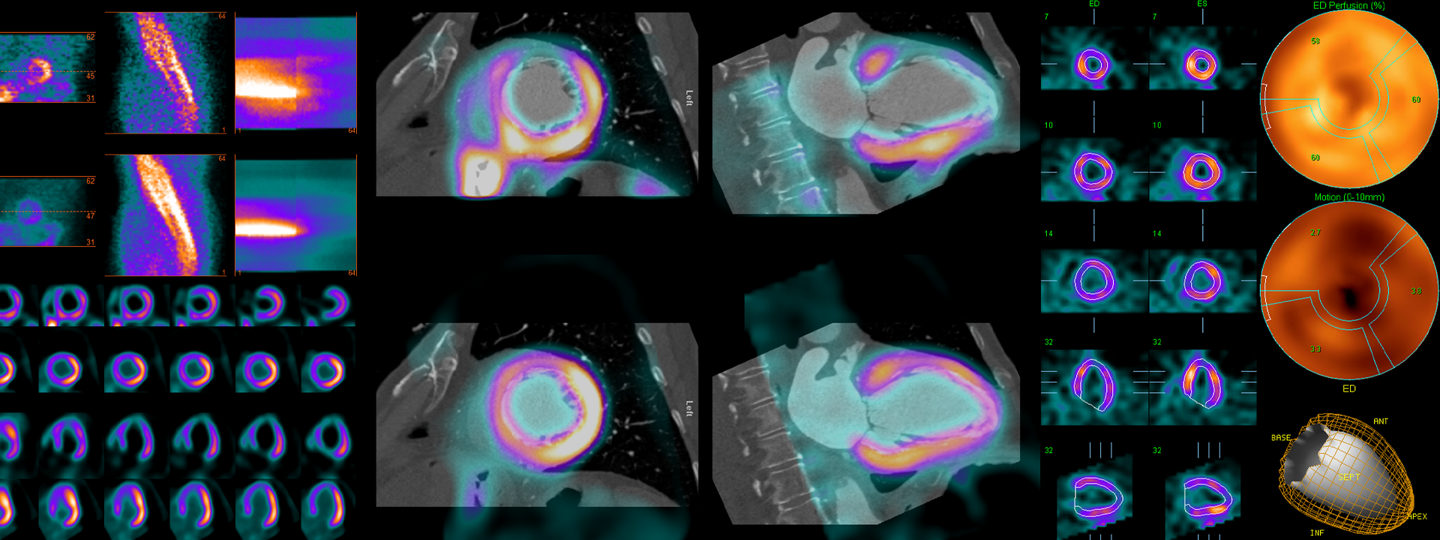

QUAD, the Quantitative Diagnostic Software Group, formerly the Artificial Intelligence in Medicine (AIM) program, is a research program of the Department of Medicine at Cedars-Sinai Medical Center. QUAD seeks to develop software to allow computers to process and analyze three-dimensional images of the heart in much the same way an experienced human operator would. - Invia Corridor4DM

Corridor4DM is state-of-the-art software for the quantification, review, & reporting of cardiac perfusion and function. 4DM establishes new precedents with its configurable user interface and delivers a comprehensive solution, mitigating the need for multiple applications.